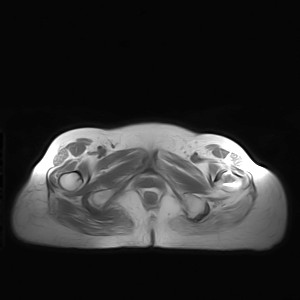

图像太差了 1、右侧臀肌旁脓肿? 建议增强 2、左侧股骨头坏死并半脱位

1、左侧股骨头坏死并髋关节半脱位;

2、右侧臀肌感染,(可能褥疮所致)